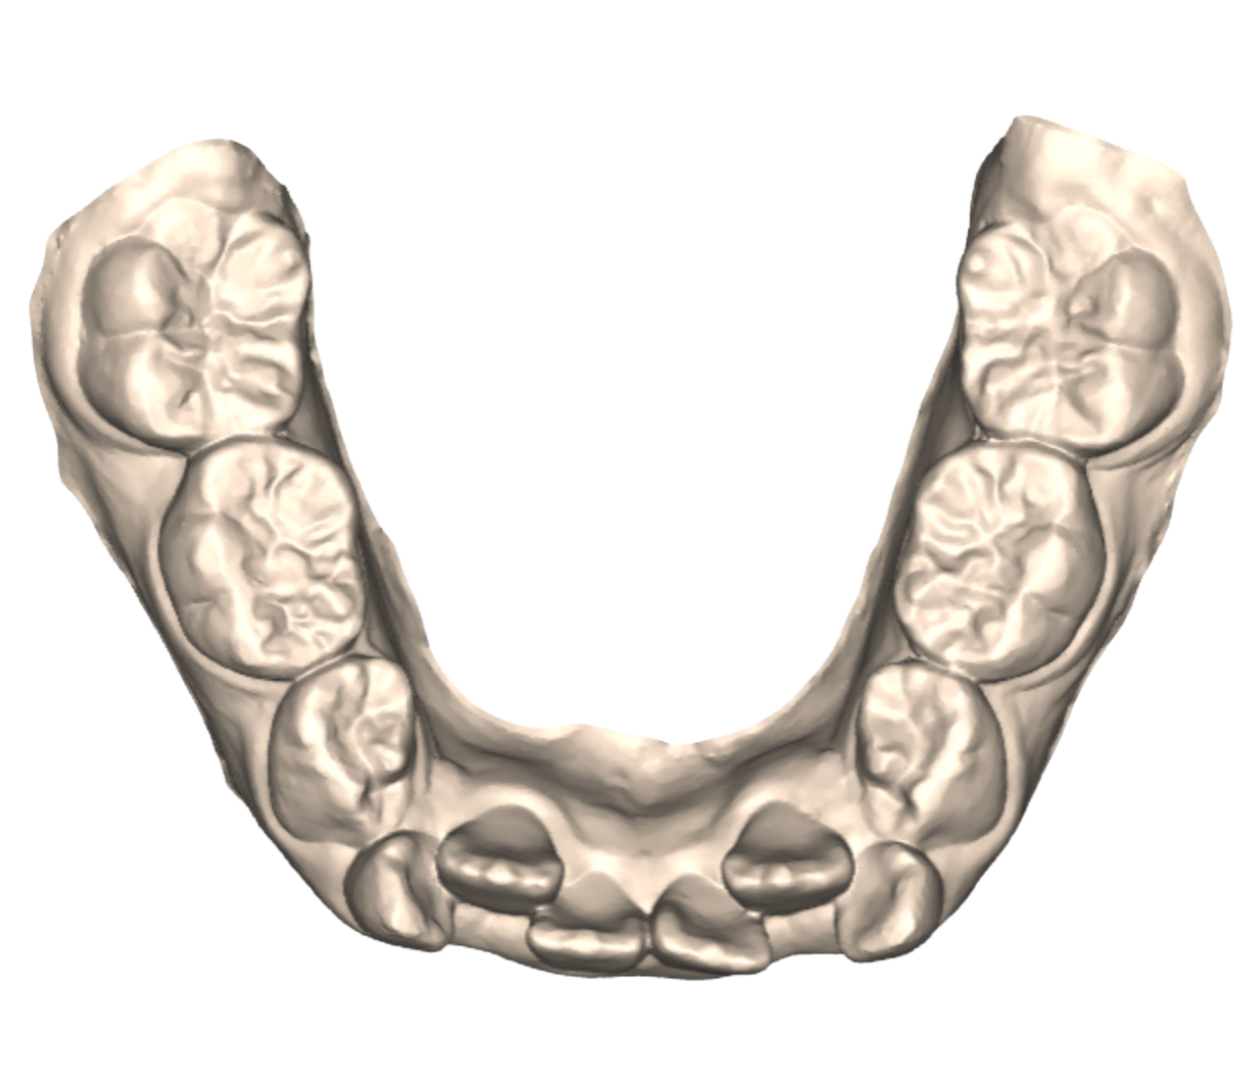

Why Age 7–10 Is a Critical Window

During this time, the jaws are still developing. This gives us as orthodontists a unique opportunity to ensure healthy development in ways that are nearly impossible to achieve later in life.

Proactive Eruption Guidance

Major Crowding

Before

Crowding Resolved

After

Dr. Gerald Kim approaches early orthodontic care with custom appliances made differently for each case. Dr. Kim helps parents understand what’s happening beneath the surface. His philosophy is conservative and intentional: intervene when necessary, monitor when appropriate, and always prioritize your child’s long-term health.